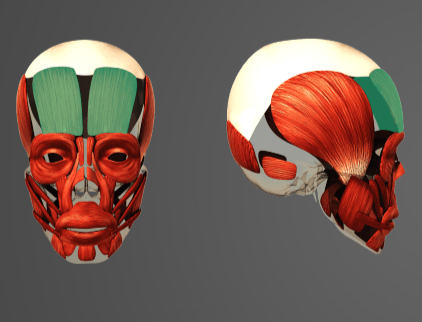

-

Question of

Určete:

-

svaly mimické

-

sval tylní

-

sval licní velký a malý

-

sval trubačský

-